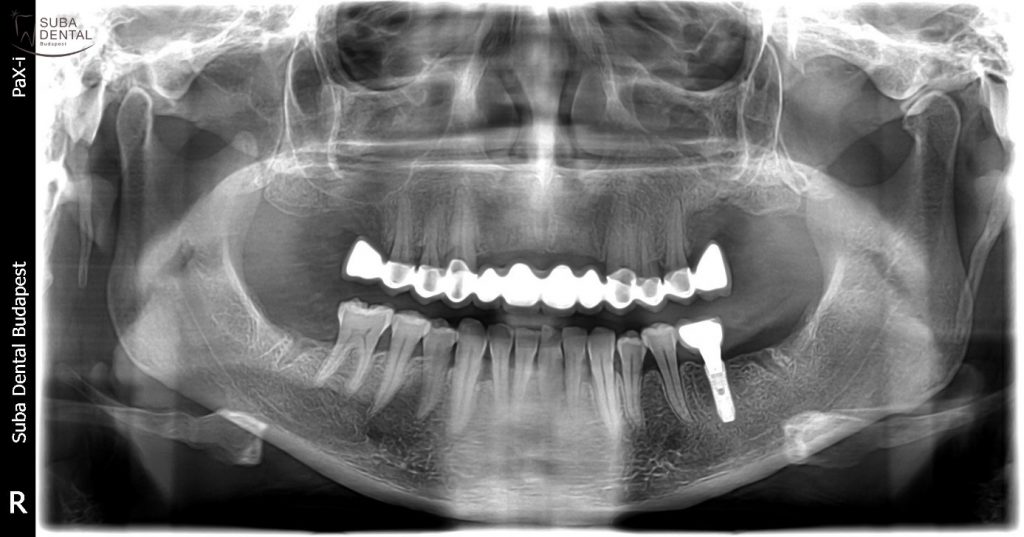

Kontroll panorámaröntgen a bal alsó nagyőrlő helyére beültetett implantátummal

A kész panorámaröntgen-felvétel a kész felső fémkerámia, és az alsó DIO implantátumra készült fémkerámia ragasztható koronával